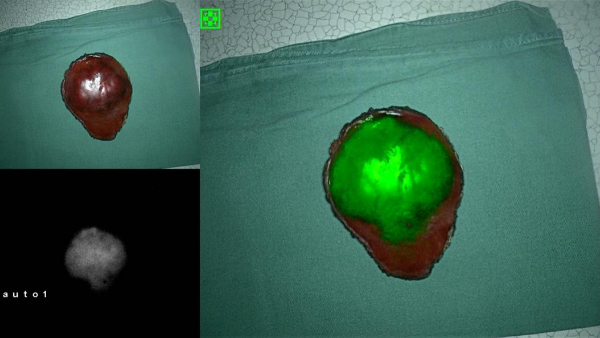

“关灯,开荧光”,随着一声指令,手术室的荧光显示器上瞬间出现了一个绿色团块,这个团块就是长在患儿肝脏上的肿瘤。随即,主刀医生在荧光的引导下,沿着荧光边缘标记肿瘤与周围正常肝脏组织的界限,并按照这条界限,将肿瘤完整切除。

近日,首都儿科研究所附属儿童医院普通(新生儿)外科首次应用小儿肝脏肿瘤吲哚菁绿荧光显像介导下术中导航技术,为一名5岁肝母细胞瘤的患儿成功切除直径5厘米的肿瘤。

吲哚菁绿(Indocyanine green, ICG)是一种水溶性近红外荧光染料,它在进入人体后与血浆蛋白结合,结合后被肝脏组织代谢,经过胆汁排出体外。正常肝组织可以很快吸收血中的ICG并排入胆道,但肝脏肿瘤组织摄取ICG后代谢缓慢,导致ICG滞留在肿瘤内,这就造成了ICG在肿瘤和正常肝脏组织内的差异。由于ICG在近红外光的照射下会显示出荧光,因此,在手术前1-2天给予患儿注射ICG,经过代谢,到手术时,ICG就单独存留在肿瘤组织内了,在近红外光的照射下,肿瘤就自行跃然肝脏上,无处遁形了。

在一片白皑皑的北极冰原上,想找到一只白色的北极熊并不容易,但这只北极熊穿上一件鲜绿色的外衣就大不一样了。看得清,自然打得准,应用此项技术,肿瘤组织与正常肝脏组织的界限泾渭分明,在切除肿瘤后,也可在荧光下探查肝脏断面是否存在绿色的肿瘤残留,以及正常肝脏上是否存在绿色的转移灶,从而减少肿瘤复发的可能。